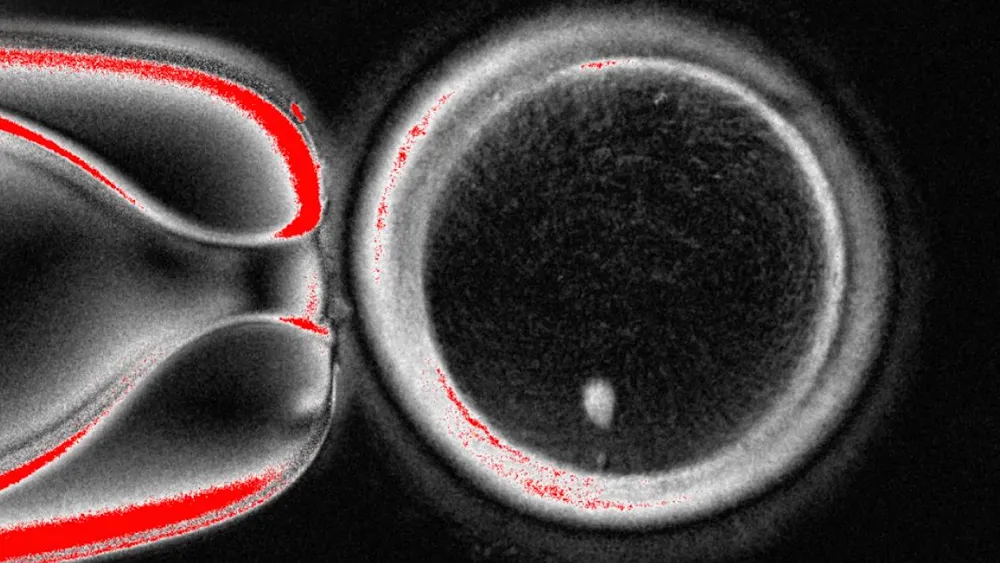

El proceso consiste en extraer el núcleo de una célula de piel humana y transferirlo a un óvulo del que se ha eliminado su núcleo. Esto fue detallado en un artículo publicado en la revista Nature Communications, donde los científicos discuten las implicaciones de su descubrimiento.

Los investigadores afirman que este nuevo método soluciona un problema que había limitado intentos anteriores de crear óvulos a partir de células no reproductivas. Los óvulos naturales contienen 23 cromosomas; sin embargo, las células de la piel contienen 46, lo que plantea un desafío en el proceso de creación.

El equipo de la Universidad de Salud y Ciencia de Oregón asegura haber encontrado la solución a este obstáculo. Introdujeron el proceso de mitomeiosis que imita la división celular natural, lo que permite que un conjunto de cromosomas se descarte, resultando en un óvulo funcional.

En un experimento, los investigadores fertilizaron 82 de estos óvulos modificados en tubos de ensayo con esperma, pero solo alrededor del 9 por ciento llegaron a la etapa de blastocisto, que es crucial para la transferencia en tratamientos de fertilización in vitro.